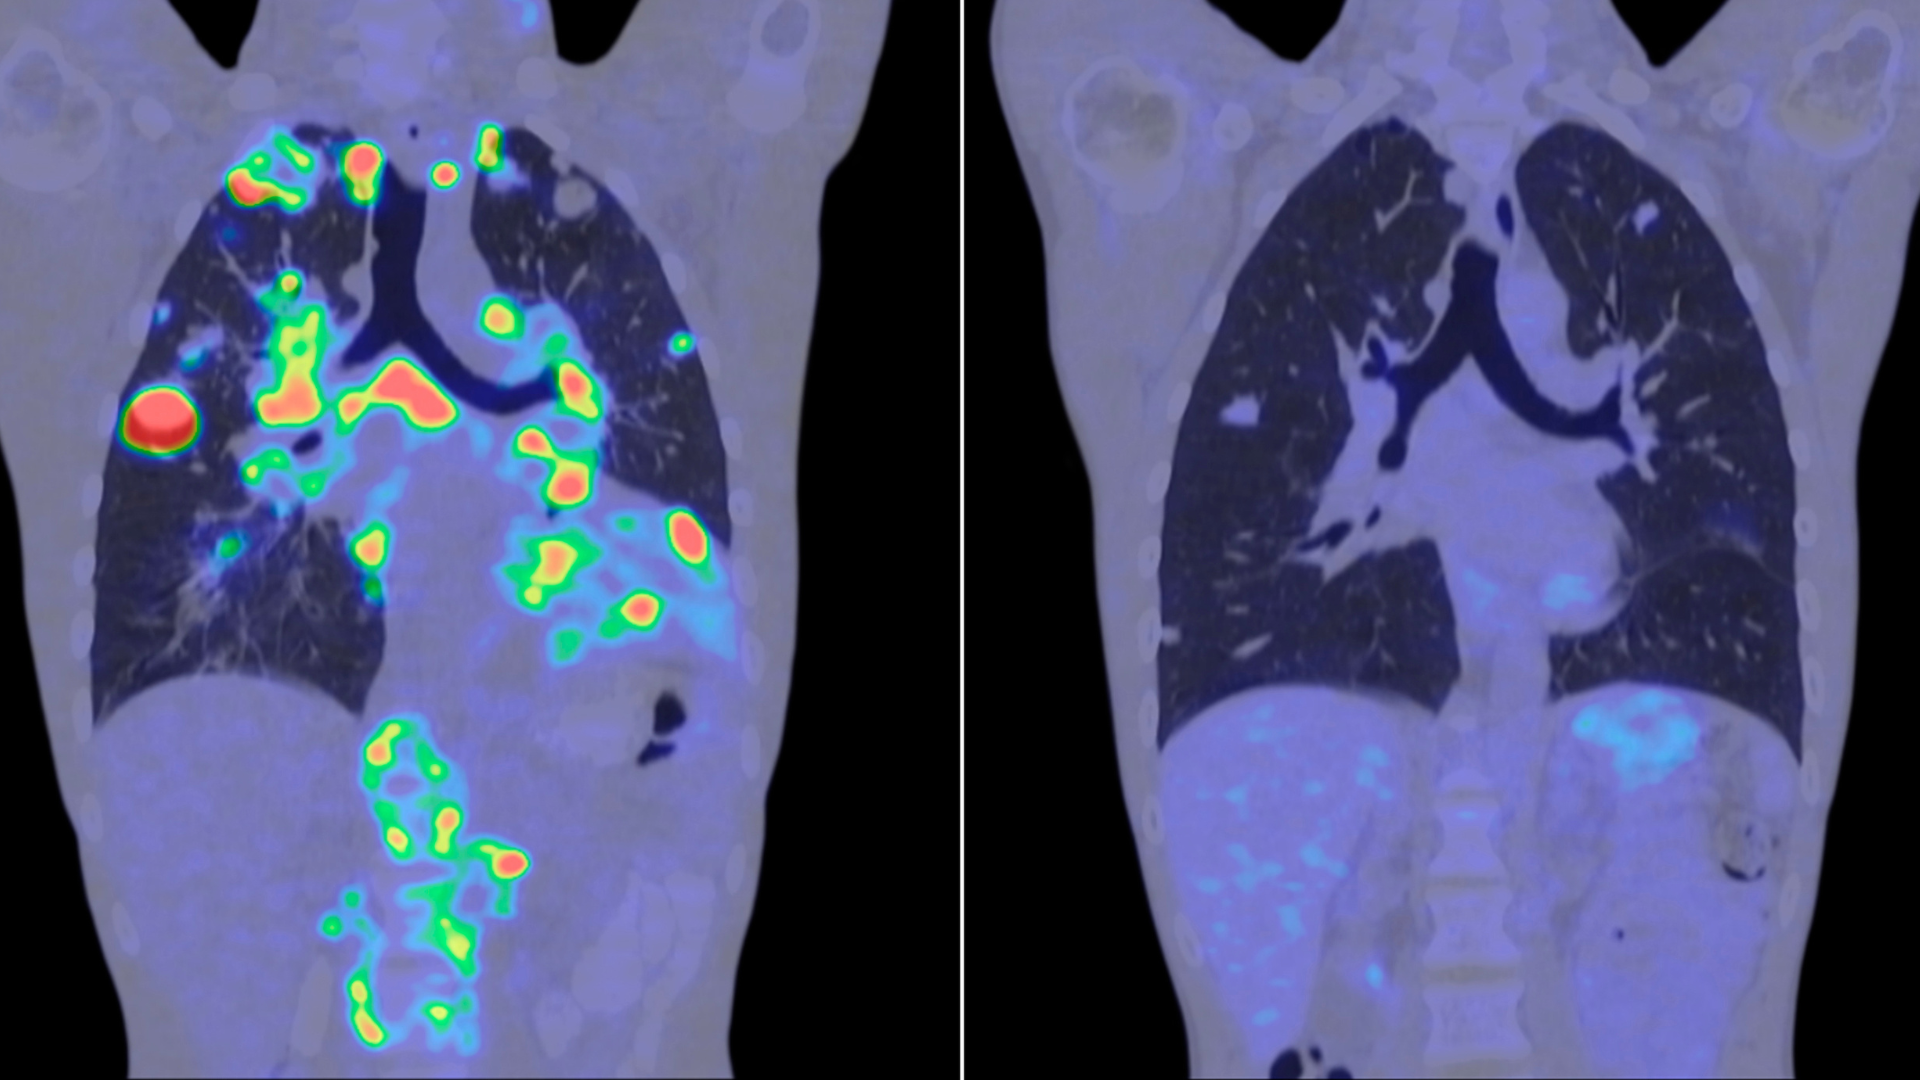

El principal impacto de la inteligencia artificial se está produciendo en el ámbito del diagnóstico precoz. Los sistemas de análisis de imágenes médicas, entrenados con miles de casos, son capaces de detectar patrones que el ojo humano puede no identificar con la misma rapidez o precisión.

En el caso del cáncer de mama, los programas de cribado son una herramienta fundamental de salud pública. La incorporación de inteligencia artificial permite optimizar estos procesos, reducir errores y mejorar la capacidad de respuesta del sistema sanitario.